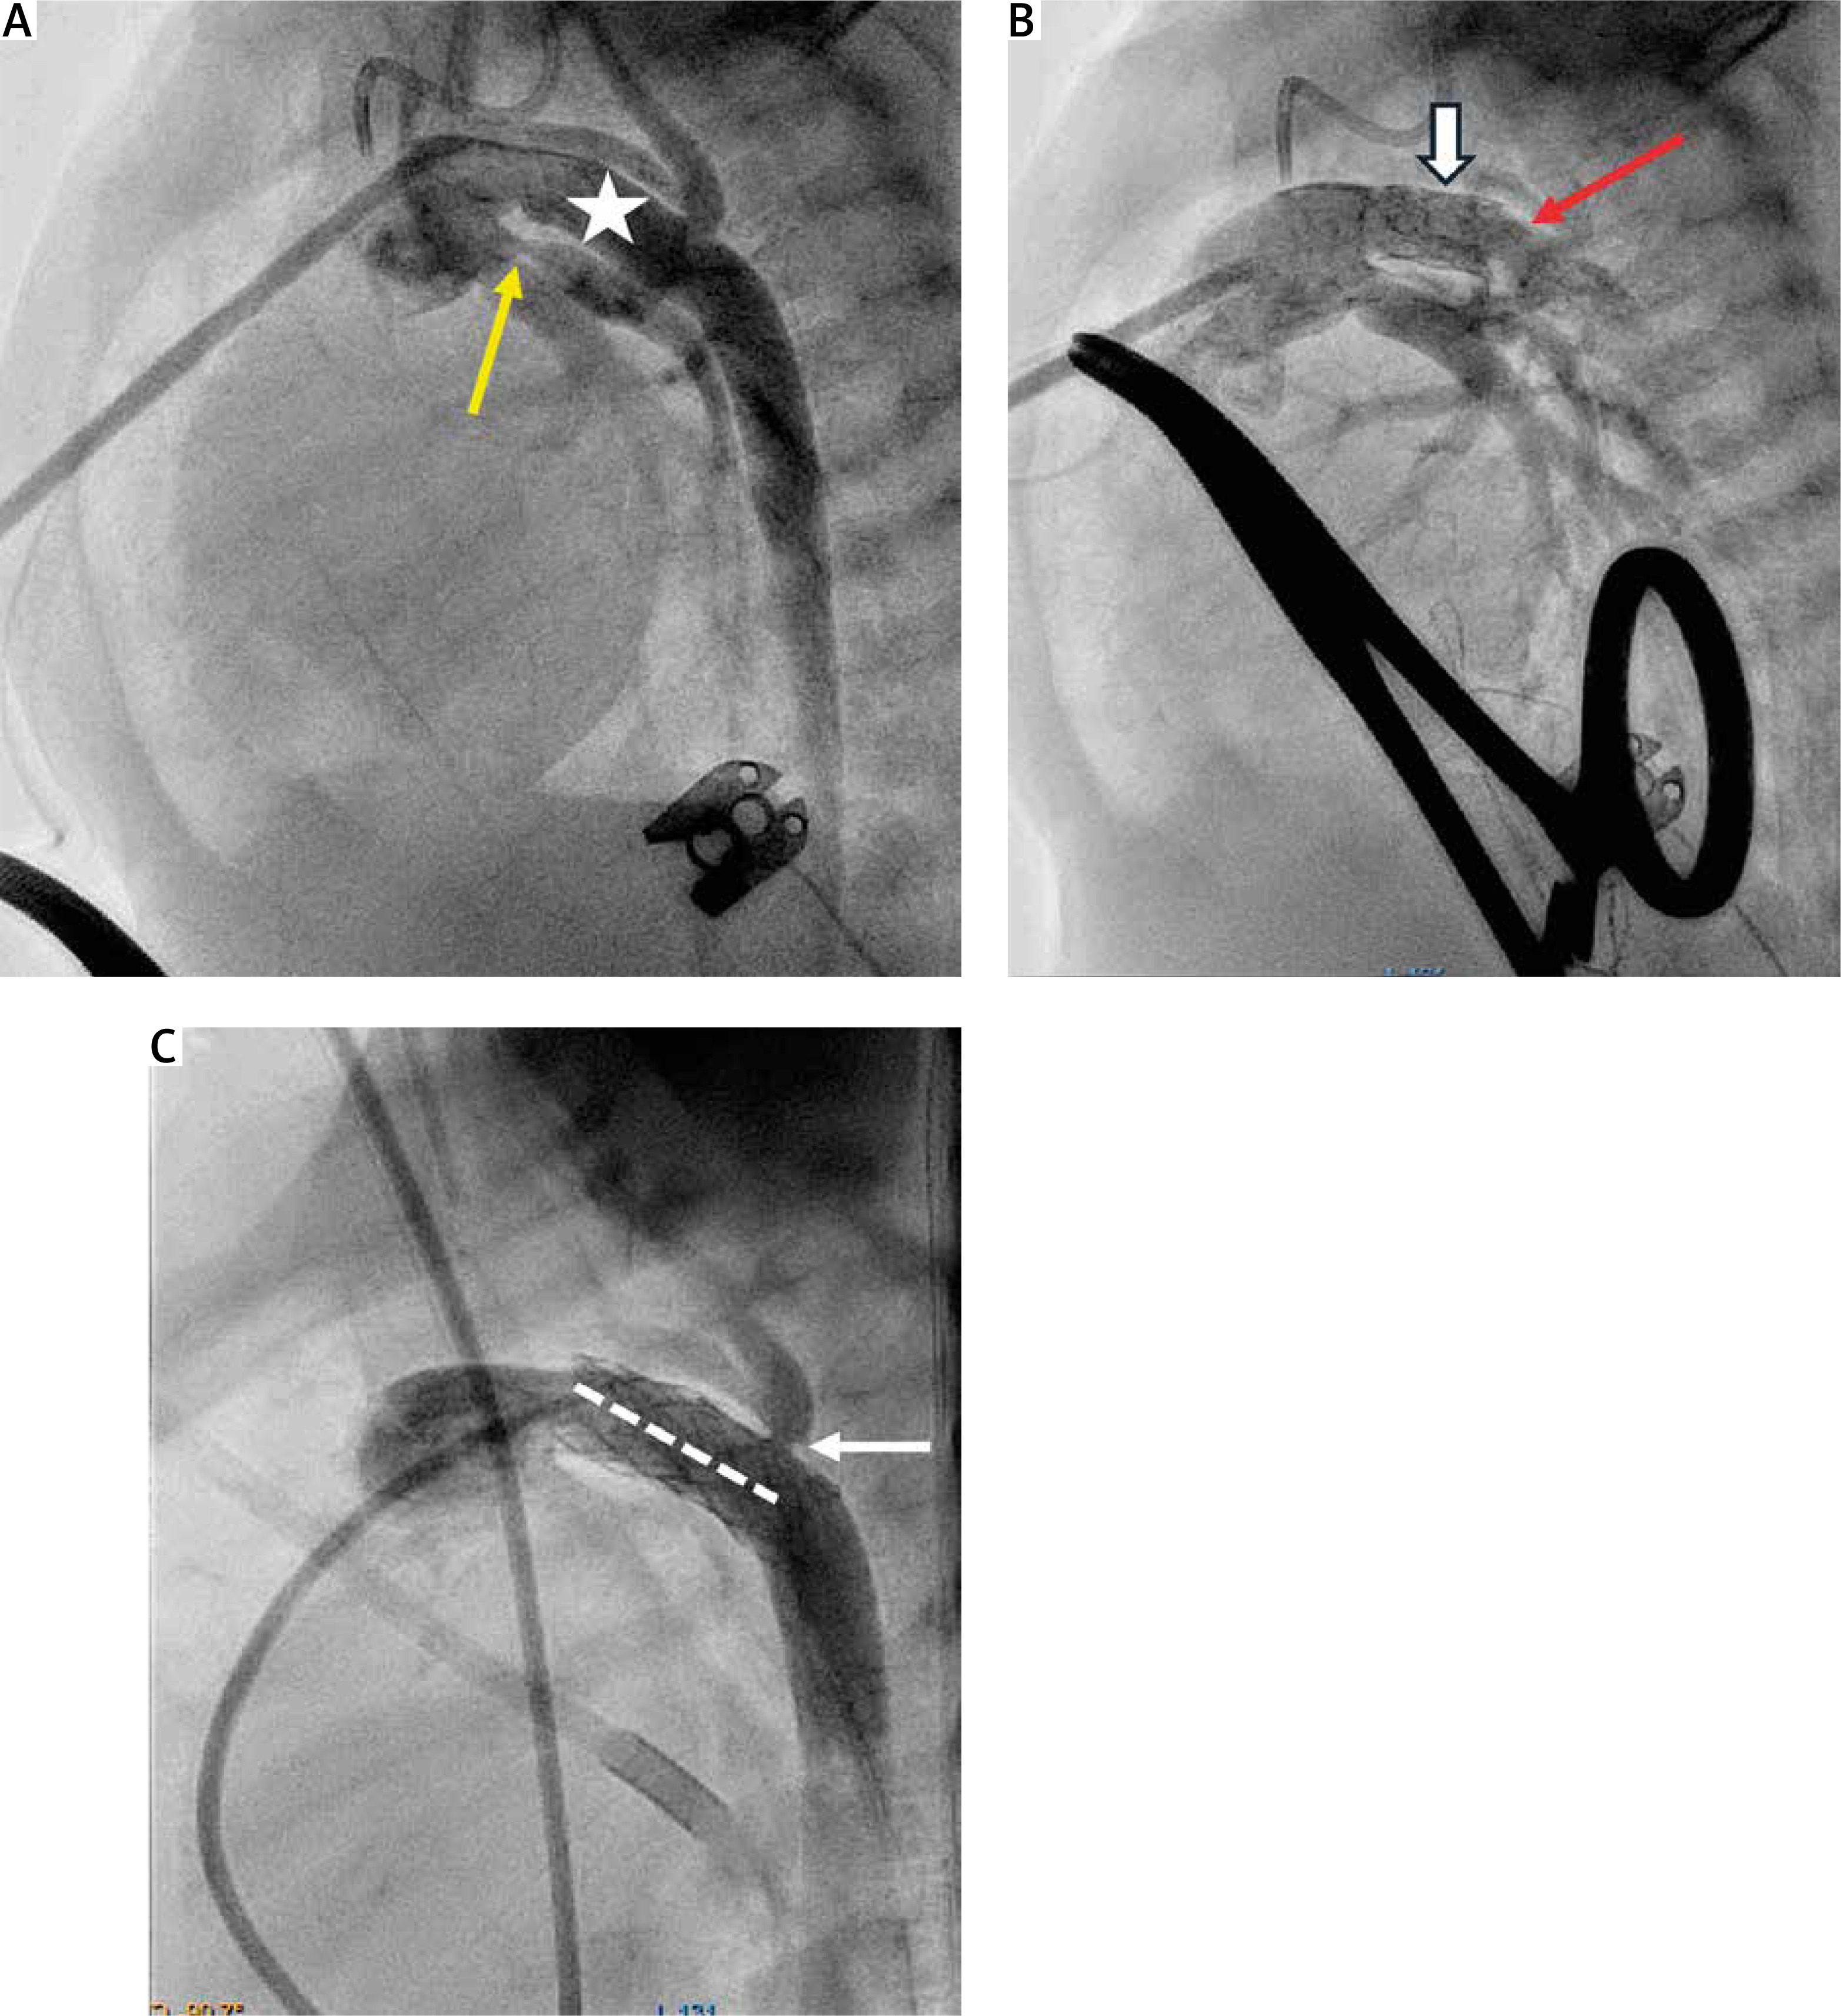

Initial percutaneous intervention, as the first stage of HP, was performed using a 6 or 7F catheter in the right femoral vein in 6 patients due to: 1) restrictive FO with BAS (n = 4), 2) intact atrial septum with septal perforation (n = 1), 3) critical aortic valve stenosis (AVS) with balloon aortic valvuloplasty (n = 2), 4) DA severe stenosis despite PGE1 infusion with Palmaz Genesis 9 mm/18 mm and 10 mm/19 mm stent deployment (n = 2). Patient 10 had a stent implanted 7 days after PAB (Figure 2).

Figure 2

Percutaneous arterial duct stent implantation. A and B in Patient 11 – Pulmonary artery angiography in lateral view showing tight pulmonary bands, mild narrowing (6.5 mm) of the arterial duct (white arrow) at the pulmonary end, and aneurysmal dilation (11.5 mm) at the aortic end. B – Pulmonary angiography following Palmaz Genesis 10 mm/19 mm stent deployment with unobturated flow (white star) and tight pulmonary bands. C and D in Patient 10 – Pulmonary artery angiography in a patient with severely stenotic arterial duct (3.5 mm) at the pulmonary end and dilation (7 mm) at the aortic end. Pulmonary arteries without bands. D – Pulmonary artery angiography following Palmaz Genesis 9 mm/18 mm stent deployment providing effective flow into the descending aorta